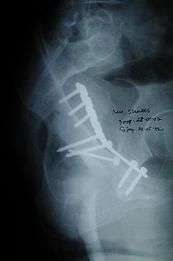

Posterior column fracture

Cause: as with posterior wall injury, this also occurs due to dash board injury.

Associated injury: There could be associated fracture of the posterior wall making this associated variety of fracture. The broken bone piece may injure the important Sciatic nerve causing paralysis of the foot, may or may not recover depending on the extent of injury to the nerve.

How to diagnose: Best seen in iliac oblique and obturator oblique views

CT scan helps in identifying impaction of bone pieces and if there are pieces in the joint

Treatment: if the femur head is dislocated, it should be reduced as soon as possible, to prevent damage to its blood supply. This is preferably done under anaesthesia, following which, leg is kept pulled by applying traction to prevent joint from dislocating.

The final management depends on the size of the fragment(s), stability and congruence of the joint.

In some cases traction for six to eight weeks may be the only treatment required

If the fragments do not fall into place, or if there are bone pieces in the joint, or if the joint is unstable, surgical fixation using screw(s) and plate(s) is performed

Post-surgery treatment: depending on the stability achieved, the person may be allowed standing and walking with help of support for about six to eight weeks.

Full function may return in about three months.

Complications: Sciatic nerve injury and stoppage of blood supply to femoral head at the time of accident or during surgery may occur. Deep vein thrombosis and pulmonary embolism are other complications that may occur in any type of injury to the acetabulum.